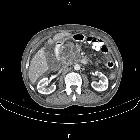

CT

They present as single or multiple pancreatic cystic hypodense lesions. Dilatation of the main duct over 5 mm is concerning for the main type IPMN. The communication with the pancreatic ducts, particularly the side branch lesions, may be difficult to demonstrate on CT. They do not calcify.

Both a dedicated pancreatic CT protocol and pancreatic MRI/MRCP have been reported having similar accuracy in the characterization of the pancreatic cystic lesions , but most recent guidelines recommend MRI as the modality of choice for IPMN followup.